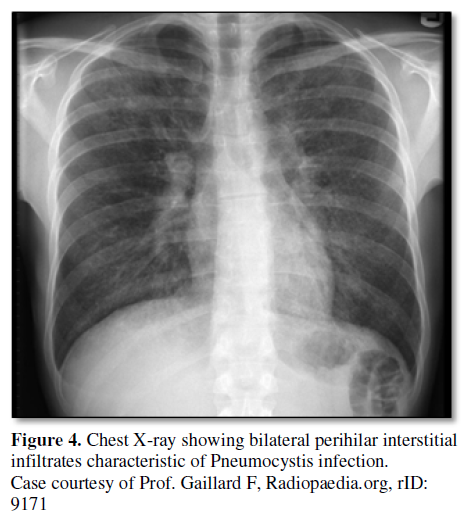

PCP usually manifests within the first 6 months after transplantation and typically presents with dry cough, breathlessness and/or hypoxemia. It is caused by is an opportunistic fungal pathogen known as Pneumocystis jiroveci (formerly Pneumocystis carinii). Universal antimicrobial prophylaxis with TMP-SMX has led to significant reduction in the incidence of post-transplant PCP. PCP is diagnosed based on clinical history, radiographic findings, sputum or Bronchoalveolar lavage (BAL) staining. Typical chest x-ray findings in PCP include diffuse, bilateral interstitial infiltrates, but other patterns may be seen (Figure 4). Detection of the organism in respiratory specimens either induced sputum or BAL fluid is done by specific staining. Staining is essential for diagnosis as pneumocystis cannot be cultured. Direct fluorescent antibody staining using a fluorescein-conjugated monoclonal antibody can visualize both trophic forms and cysts. Other staining used for detection of trophic forms includes Gram-Weigert, Wright-Giemsa or modified Papanicolaou stains. Cysts can be stained with calcofluor white, cresylecht violet, Grocott-Gomorimethenamine silver or toluidine blue. In rare cases, lung biopsy with tissue stain and PCR is used for diagnosis. There are different types of PCR assays available for the detection of Pneumocystis in induced sputum or BAL fluid, blood or nasopharyngeal aspirate. These techniques increase the rate of detection of Pneumocystis by 7% over BAL staining [50]. Another test used in diagnosis of PCP include beta D-glucan assay. Beta D-glucan is a cell wall component of most fungi including PCP. Serum beta D-glucan assay has a high negative predictive value with sensitivity of 92% and specificity of 86% in detecting PCP [51,52].